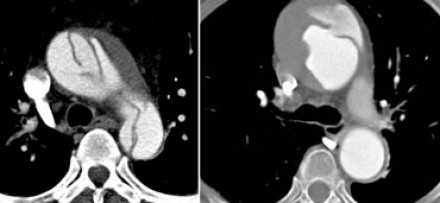

![11]()

- Слева представлен пациент со Stanford A. Диссекция с четкой визуализируемой интимой.

- Справа представлен пациент со Stanford B. Патология локализована в нисходящей аорте. «Точка входа» расположена ниже уровня левой подключичной артерии.